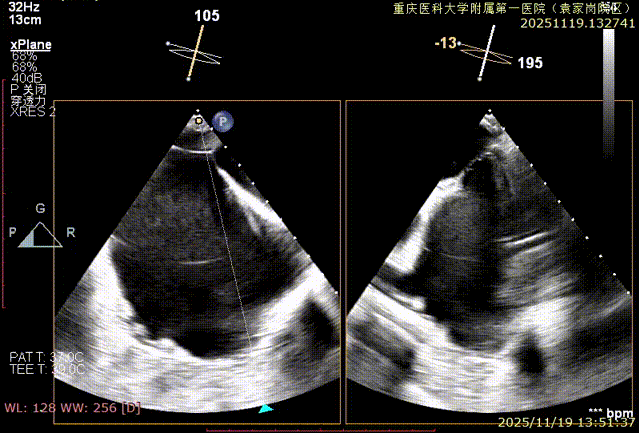

二尖瓣术前评估

复查TTE及TEE检查进一步评估二尖瓣情况。明确为FMR( Carpentier Ⅲb型),二尖瓣后叶栓系,2区瓣叶运动(视频2),重度FMR(4+), 肺静脉逆向血流;2区后叶长度1.15cm,2区前叶长度2.46cm,AP径3.2cm,瓣口面积5.1cm²,房间隔高度3.95cm,瓣叶无钙化,二尖瓣瓣膜条件适合行TEER手术。

图1、图2:2区瓣叶长度(前叶长度2.46cm,后叶长度1.15cm)及彩色血流

图3:房间隔可用高度>4cm